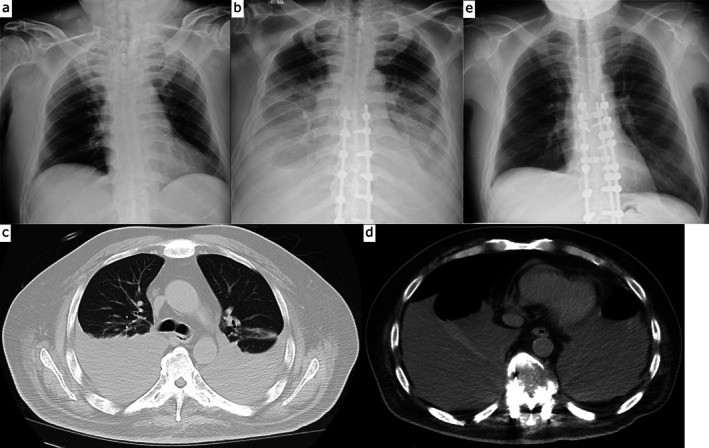

一例71岁男性弥漫性特发性骨骼肥厚症(DISH)患者因跌倒导致胸椎融合段骨折,接受后路脊柱固定治疗。术后1个月,患者因双侧大量胸腔积液和骨折部位移位较术后立即增加而再次入院。渗出性积液以淋巴细胞为主。进一步的评估表明,由于脊柱不稳定引起的炎症和胸膜刺激是可能的原因。翻修固定导致积液的溶解。低能量创伤引起的椎体骨折,如跌倒,很少导致脊柱不稳定,严重到足以引起胸腔积液,即使在不愈合的情况下也是如此。然而,由于脊柱强直和骨骼脆弱,DISH患者更容易发生高度不稳定骨折。即使在手术固定后,这种骨折也可能进一步发展为不稳定。我们报告一个病例,这种不稳定性导致局部炎症和胸膜刺激,最终导致双侧胸膜积液。DISH常见于老年人,与肥胖和糖尿病有关。据报道,其流行率正在上升。因此,内科医生和骨科医生都应该意识到类似病例的可能性,并在鉴别诊断和处理不明原因的胸腔积液时考虑与DISH相关的脊柱不稳定。

A 71-year-old man with diffuse idiopathic skeletal hyperostosis (DISH) underwent posterior spinal fixation for a thoracic vertebral fracture at a fused segment, sustained as a result of a fall. One month postoperatively, he was readmitted due to bilateral massive pleural effusions and increased displacement at the fracture site compared to the immediate postoperative state. The effusions were exudative and lymphocyte-predominant. Further evaluation suggested that inflammation and pleural irritation due to spinal instability were the likely causes. Revision fixation led to the resolution of the effusions. Vertebral fractures caused by low-energy trauma, such as a fall, rarely result in spinal instability severe enough to cause pleural effusion, even in cases of nonunion. However, patients with DISH are more prone to highly unstable fractures due to spinal ankylosis and bone fragility. Even after surgical fixation, such fractures may progress to further instability. We report a case in which this instability led to localised inflammation and pleural irritation, ultimately resulting in bilateral pleural effusions. DISH is commonly seen in older adults and has been associated with obesity and diabetes mellitus. Its prevalence is reportedly increasing. Therefore, both internists and orthopaedic surgeons should be aware of the potential for similar cases and consider spinal instability related to DISH in the differential diagnosis and management of unexplained pleural effusions.